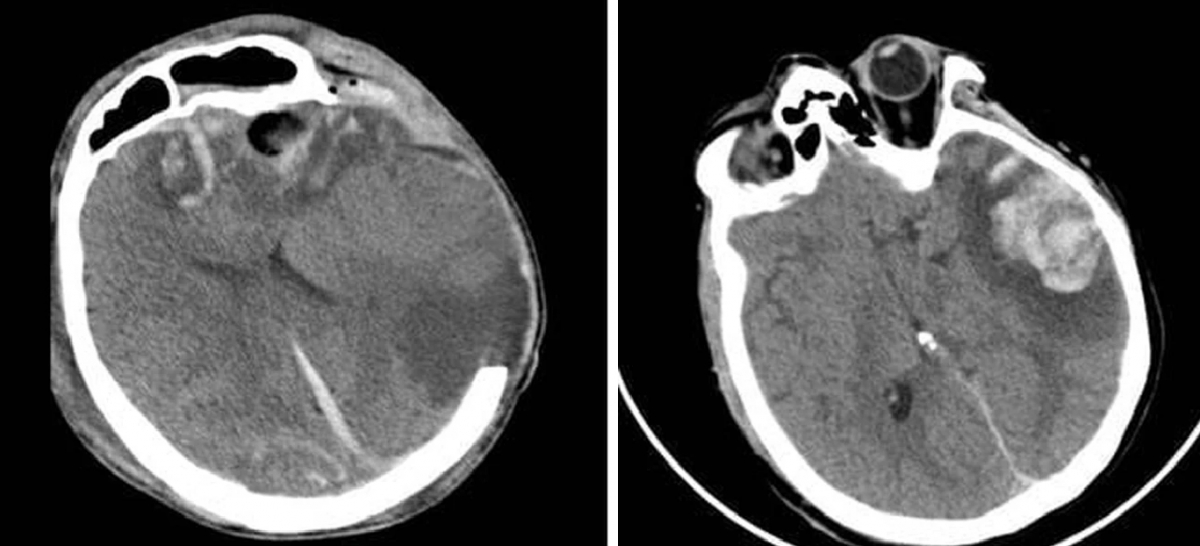

Upon admission, G.A. was in a deep coma, required mechanical ventilation and suffered multiple cerebral haemorrhages with severe brain swelling, doctors said, describing his condition as extremely critical with a high risk of death.

His mother sustained a large temporal brain contusion and showed signs of impaired consciousness. Following medical consultation, doctors opted for conservative treatment. Her condition gradually improved, with recovery of awareness, communication and language function. She was discharged after 10 days of treatment.